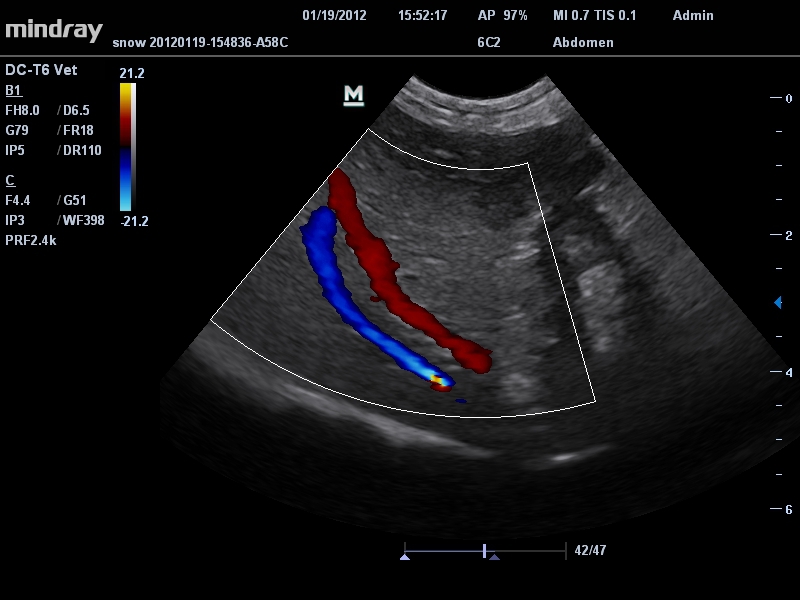

Mindray DC-T6

Ультразвуковая система Mindray DC-T6 – это инновационный аппарат для проведения высокого уровня диагностики с качественной визуализацией и широким спектром применения. Платформа рекомендована для использования в коммерчески многопрофильных медицинских учреждениях и государственных лечебных клиниках.

Ветеринария:

Да

• Режимы сканирования: B/M/CFM/PDI/Направленный PDI/PW, HPRF, Тканевая гармоника, М- и цветной М-режим.

• Микроконвексный датчик Mindray 6C2